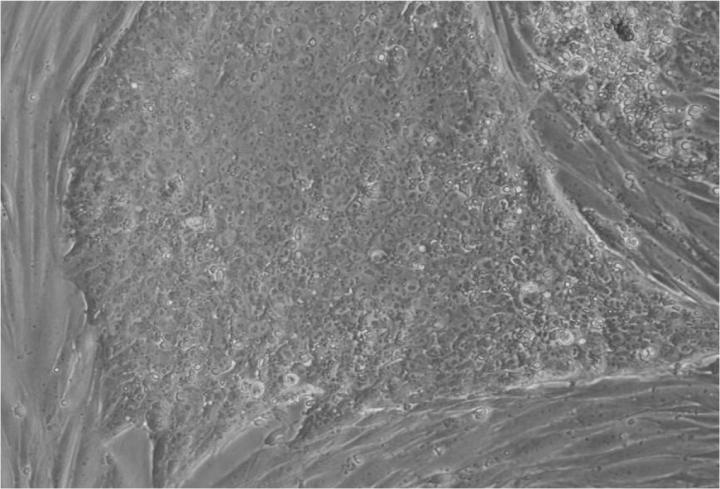

Jenny Nichols 拍攝的人類囊胚和人類胚胎干細胞圖像。愛丁堡大學 MRC 再生醫學中心向 SCNT 和多莉羊注射細胞核。